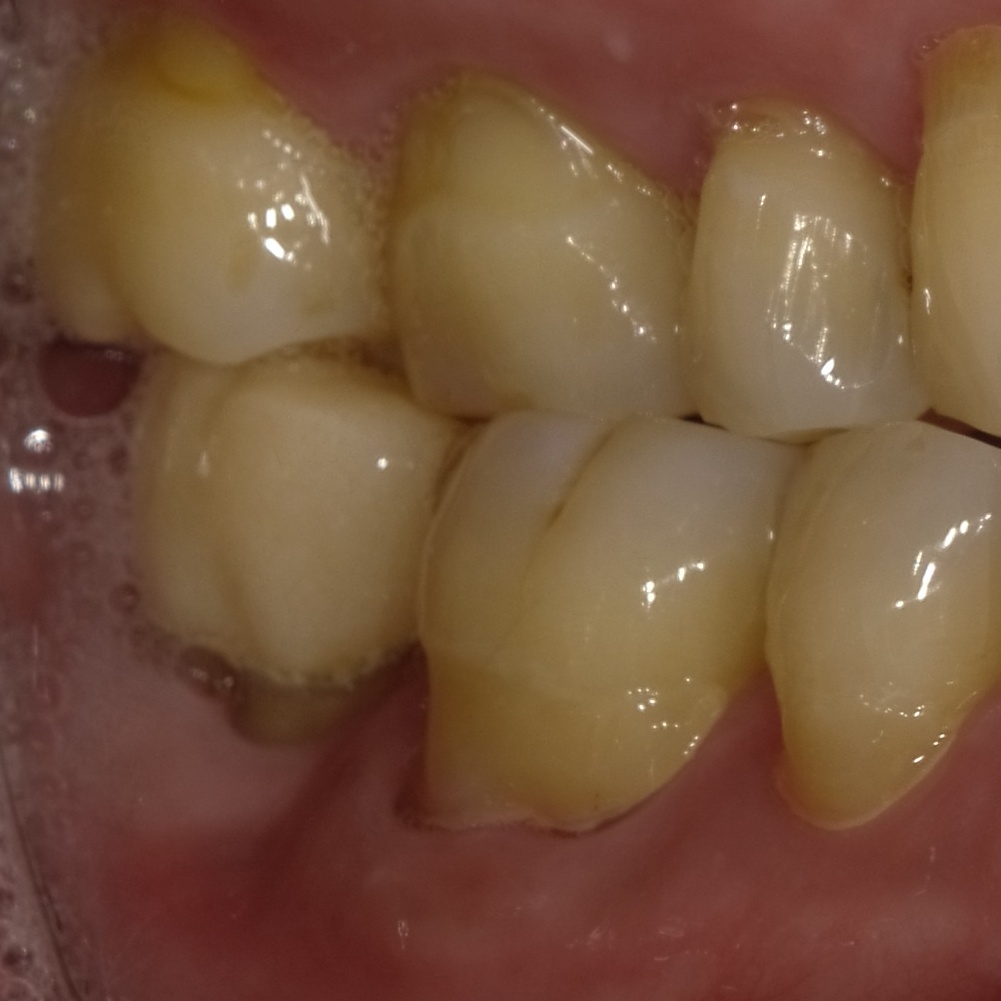

写真は歯茎にできたできもの(サイナストラクト)です。